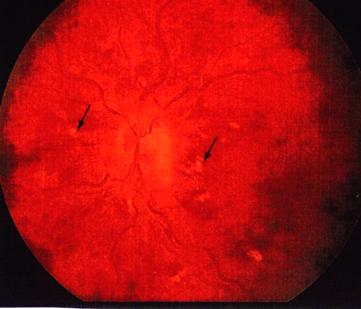

Fig. 1

Obstructie de vena centrala a retinei